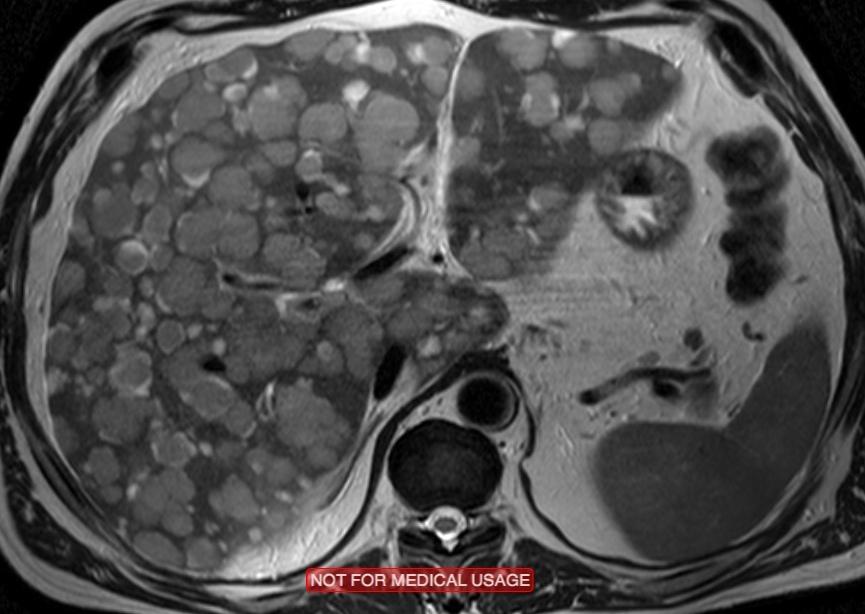

Методы динамического контрастирования печени на МРТ

Раздел: Снимки-подсказки